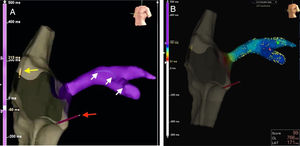

(A) Real-time visualization of catheter location (red arrow pointing to right ventricular lead, and yellow arrow to right atrial lead) and the VisionWire (Biotronik) inside the coronary sinus branches (white arrows); (B): electrical activation mapping of coronary sinus branches with guidewire and identification of the latest ventricular activation (mid segment of the lateral branch, dark blue).

In this case the use of a 3D electroanatomic system with the VisionWire additionally enabled LV activation to be mapped, and guided optimal LV lead implantation toward segments of delayed LV activation (QRS width reduced from 165 ms to 100 ms with CRT on). This implantation approach allows a greater reduction in fluoroscopy and angiography times2–4 compared with the traditional technique of CRT implantation.